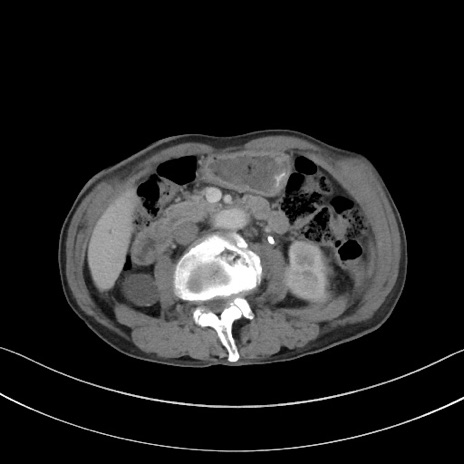

症例3(横断像)

【症例】 70歳代男性

【主訴】右鼠径部腫瘤、疼痛

【現病歴】本日朝より上記主訴あり、受診。

【既往歴】膀胱癌にて膀胱全摘、両側尿管皮膚瘻